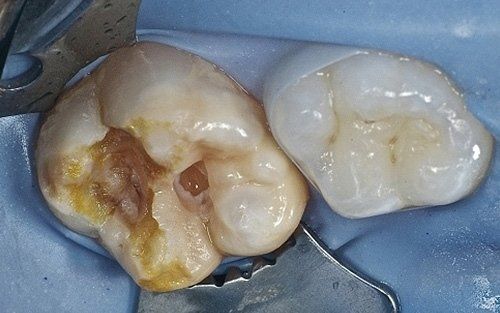

Despite the first signs having been noticed by practitioners at the end of the last century, we can consider the hypomineralisation of molars and incisors (M.I.H. - Molar Incisors Hypomineralisation) as a condition of children in the 2000s. It is characterised by insufficient mineralisation, especially of the first permanent molars, which appear with white-yellowish or brown spots and enamel that is very "porous," lacking the protective shield necessary for the health of these teeth. This leads to a greater tendency for decay, but above all, to structural breakdown of the affected areas under chewing load.